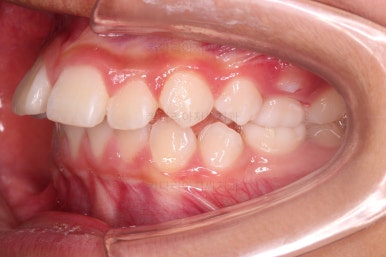

부산소아교정 초진 시 입안의 모습입니다.

윗니가 아랫니보다 많이 앞에 나와있고요.

심지어는 틈새가 벌어지기까지 했습니다.

윗니가 배열 되어있는 U자 형태(그릇 형태)가 아랫니보다 좁은 양상이고요.

이런 앵글씨 2급 부정교합에서는 아랫니가 윗니와 만나기 위해 솟구쳐서 과개교합(아래 앞니가 윗니 뒤쪽으로 깊숙히 올라가 있는 상태)이 나타나기까지 합니다.